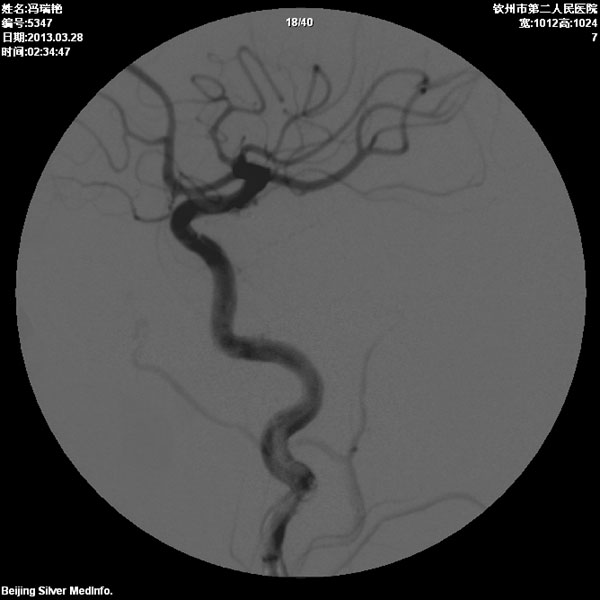

颈内动脉狭窄术前

颈内动脉狭窄术后